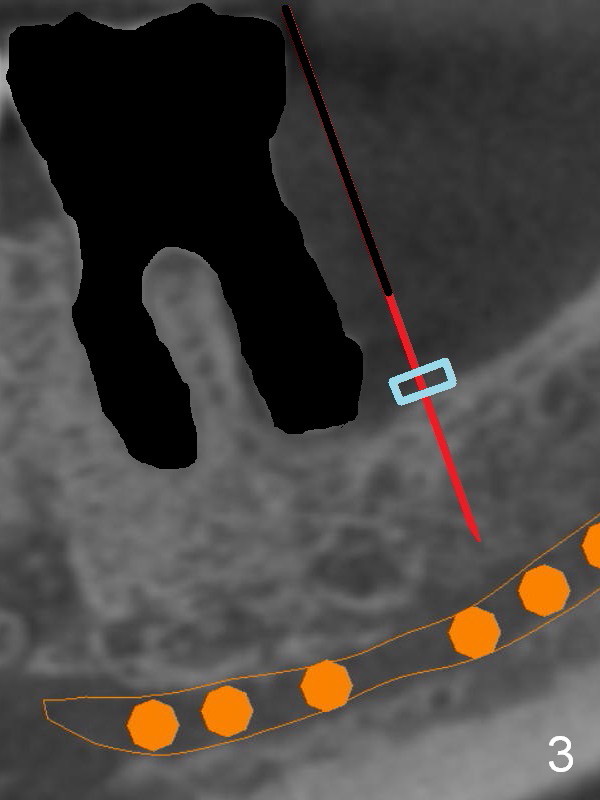

There is severe bone resorption around the distal root of the lower left 1st molar of the 56-year-old man (WG), while the loss of the 2nd molar is associated with limited bone height (Fig.1). A 5x14 mm implant will be placed at the mesial socket of #19 and 5.9 or 6.4x6 mm one is at the mesial site of #18 (Fig.7-9). Use a 2 mm pilot drill with 6 mm stopper from Sinus Master Kit (with extension) to initiate osteotomy at #18 immediately distal to the crown of #19, parallel to the long axis of the latter (Fig.2). After inserting a parallel pin at #18, extract the tooth #19 (Fig.3, antibiotic pending) and start osteotomy with a 2 mm pilot drill with 14 mm stopper (Fig.4). Insert the calibrated parallel pin at #19 (Fig.5) and measure the distance between the two parallel pins (approximately 10 mm, Fig.7). Sequential osteotomy and application of the Tatum taps (Fig.6 red rectangle) will push the septum distal (green arrow). As to #18 osteotomy, trephine, final and tap drills are to be used with control of the depth: 6 mm (Fig.7,9).